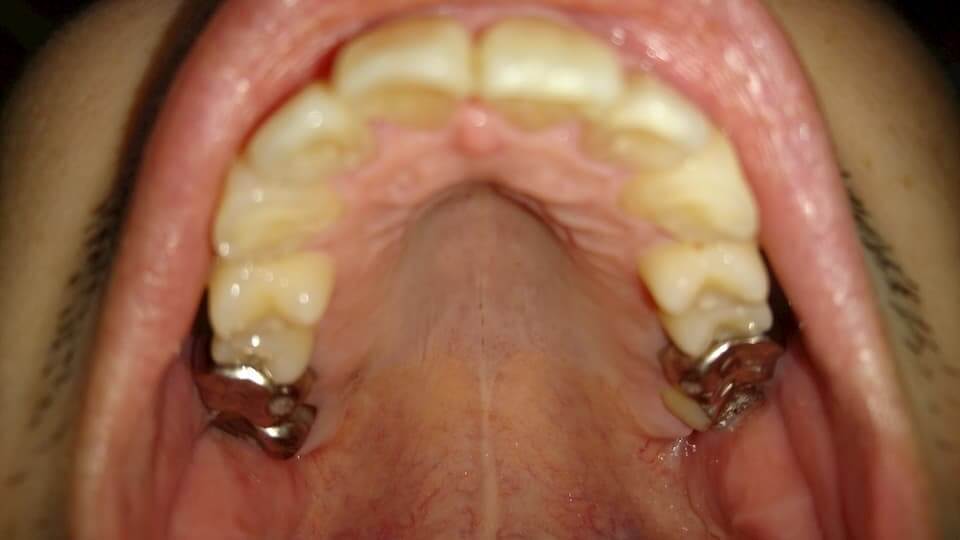

歯の写真

2019年9月2日と2020年11月26日(本日)の比較。

上で書いた稜線の話はこの画像の方がわかりやいと思う。